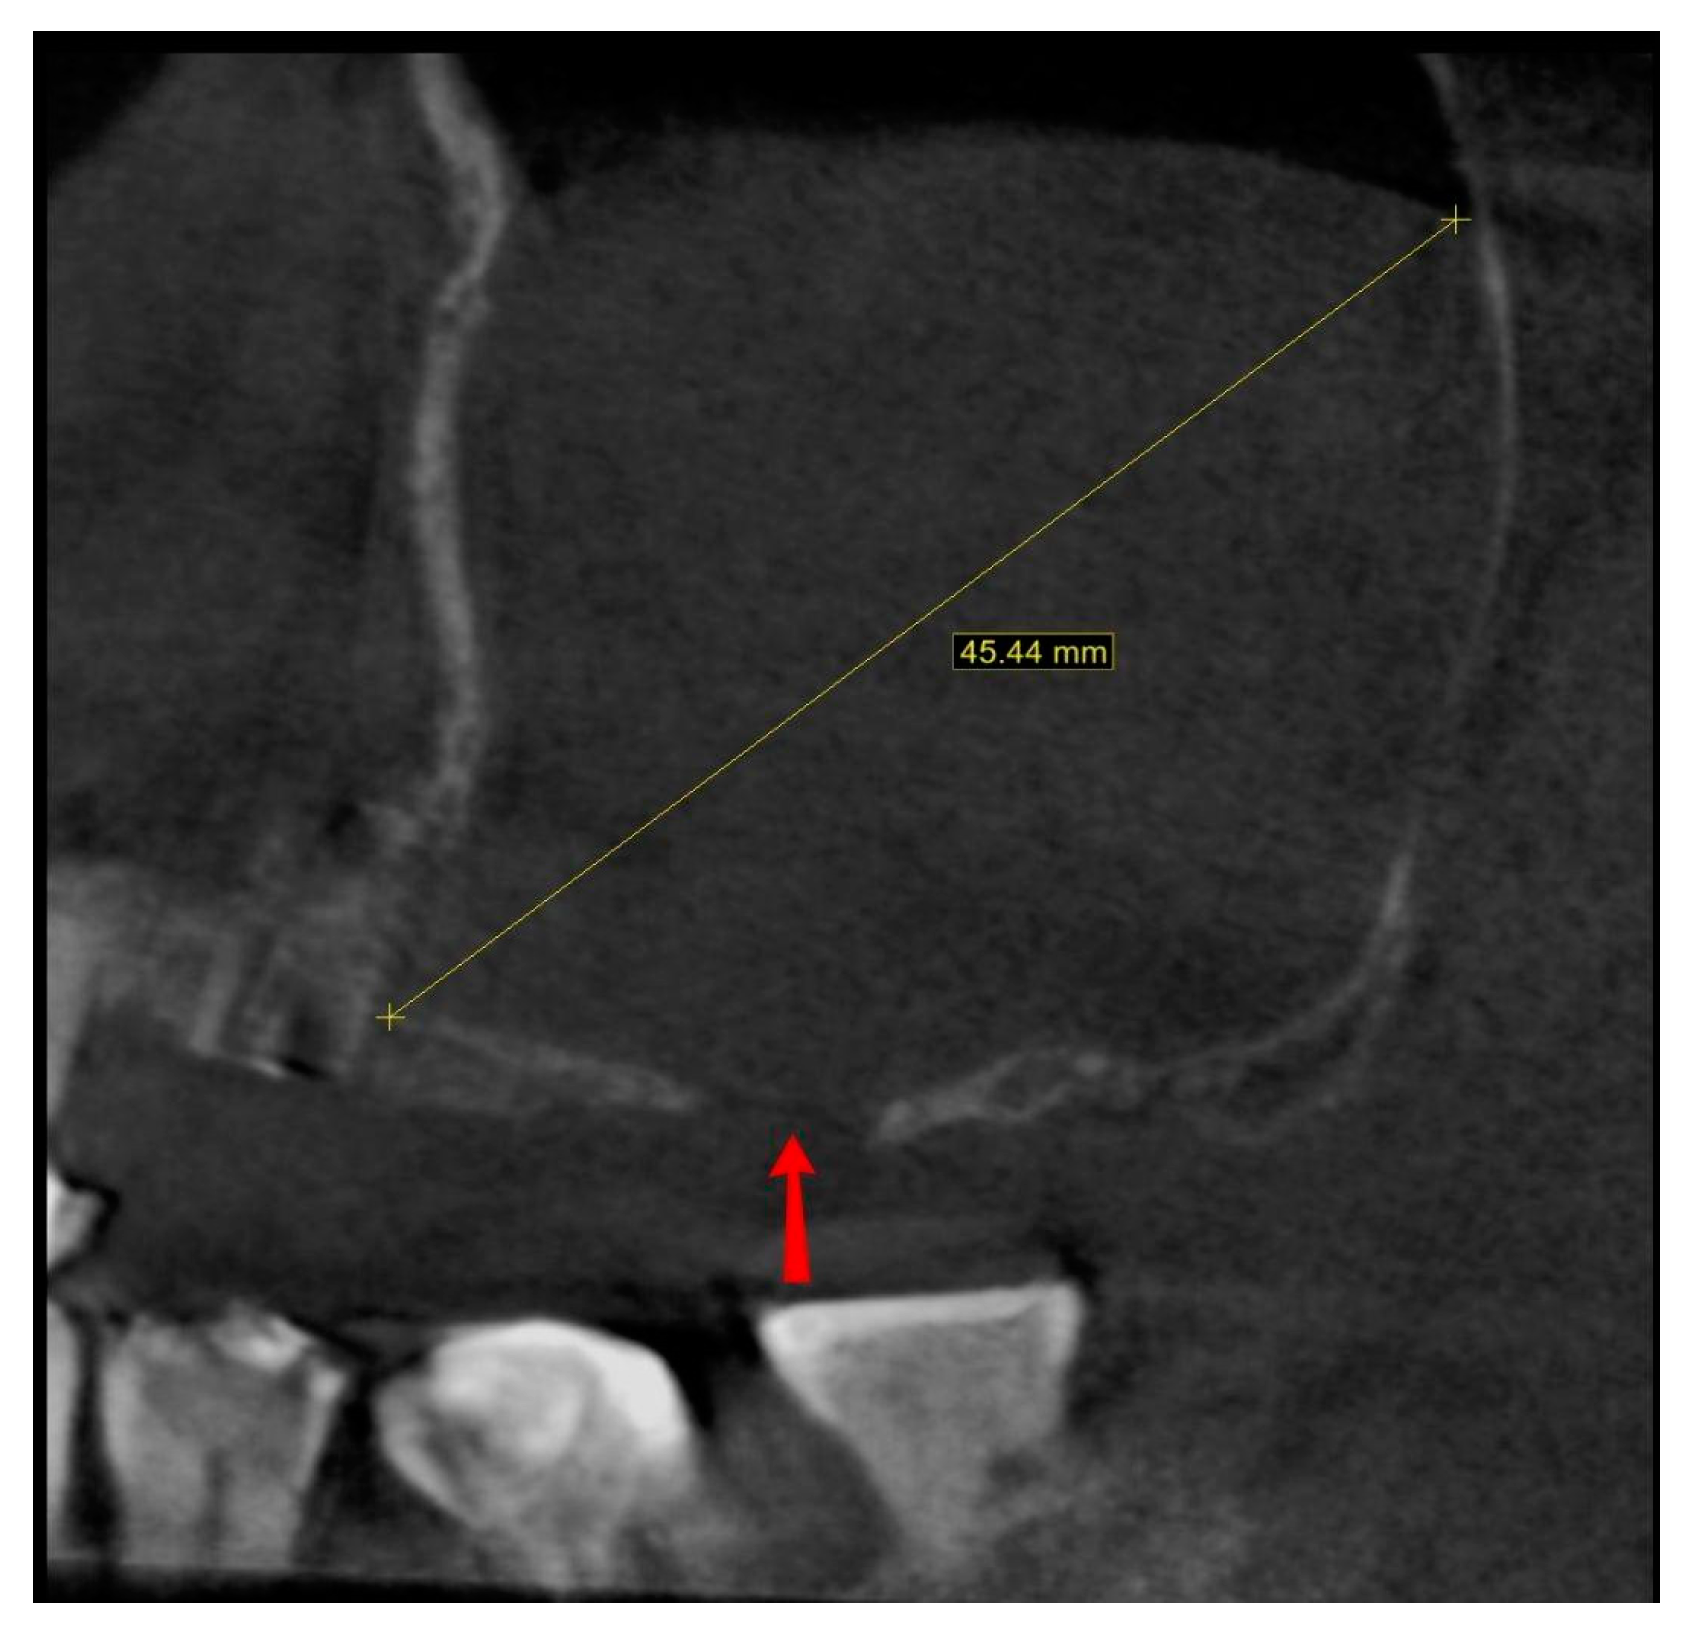

The last presented case (by A.N.) is the variation of the final version of the CET. It shows effectiveness even against a large (45.44 mm maximum diameter) retention cyst (Figure 14). Moreover, the sinus lift part was guided by a surgical guide (Figure 15), which indicated the ideal position of the window. The decision to conduct the surgery with a guide was dictated by the potential risk of the nonoptimal location of the osteotomy due to a lack of teeth or other reference points in that area. Lastly, this case presented another difficulty in the form of past oroantral communication (OAC) (Figure 16), which, from the very beginning, sentenced the surgeon to deal with another perforation of the Schneiderian membrane.

Figure 14. Screenshot from the pre-op CBCT scan showing maximal retention cyst’s diameter (45.44 mm; yellow line). Also, the past oroantral communication window is visible (red arrow).